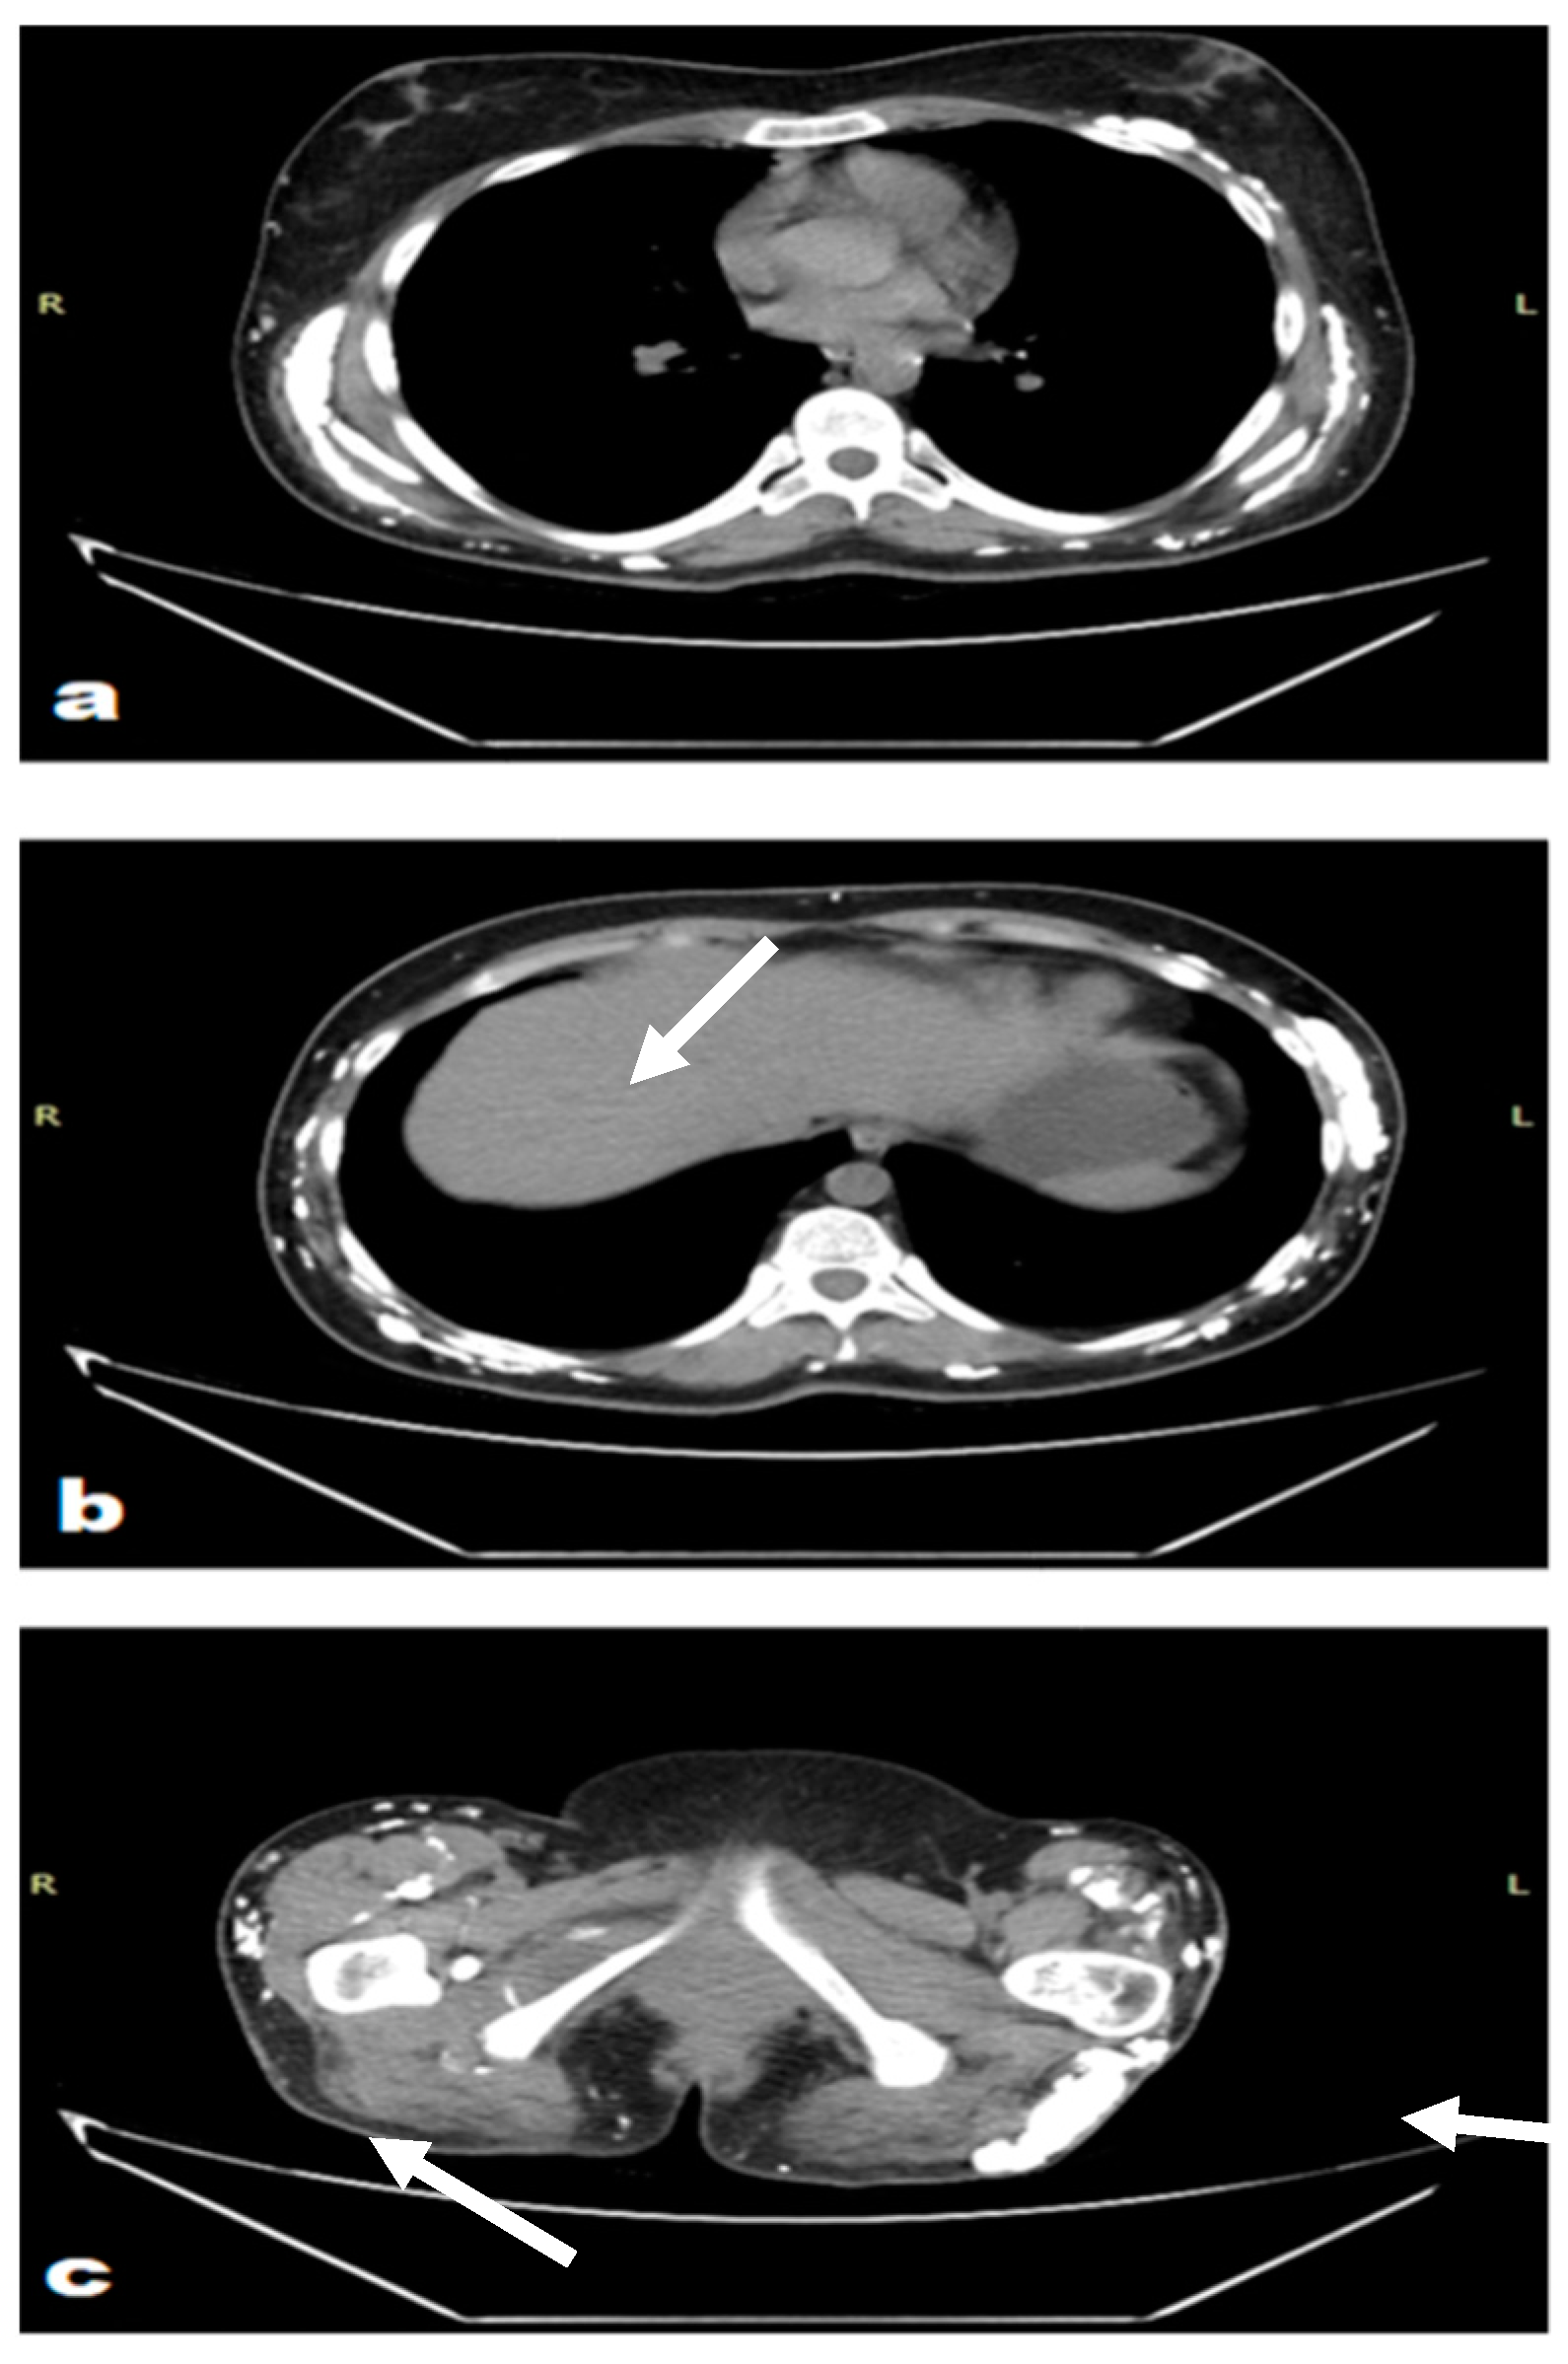

| Patient 1 | M | 71 | Hepatosteatosis, vitamin B12 deficiency, gastropathy, hiatal hernia, sigmoid diverticula, hypertension, hyperlipidemia, CTCL in remission, right-sided inguinal hernia operation (2020), prostatectomy due to prostate cancer (2014), cataract surgery and posterior vitrectomy (2014) | Periodic muscle weakness, swelling of the face and numbness with tingling in the fingers. Gottron’s papules, calcinosis, ectropion, thinned skin on fingertips with ulcers | Intravenous immunoglobulin 2 mg/kg | 2019–2021 and 2022–2022 |

| Methotrexate 12.5 mg/week with prednisone 10–15 mg/day | 2019–2022 | |||||

| Rituximab 1 g with hydroxychloroquine 200 mg | 2022–2022 | |||||

| Mycophenolate mofetil 1 g/day | 2022–2022 | |||||

| Intralesional 25% sodium thiosulfate with platelet-rich plasma 3 mL | 2023–2023 | |||||

| Surgical operation of ectropion | 2023–2024 | |||||

| Patient 2 | F | 24 | Nephrolithiasis, hepatosteatosis, steroid-induced glaucoma | Progressive weakness, calcinosis | Methotrexate 25 mg/week | 2013–2013 and 2014–2016 |

| Cyclosporine (unknown dose) | 2013–2014 | |||||

| Pamidronate (unknown dose) | 2013–2016 | |||||

| Intravenous immunoglobulin 2 mg/kg | 2013 and 2022–2023 | |||||

| Prednisone 5 mg/day | 2016–2024 |